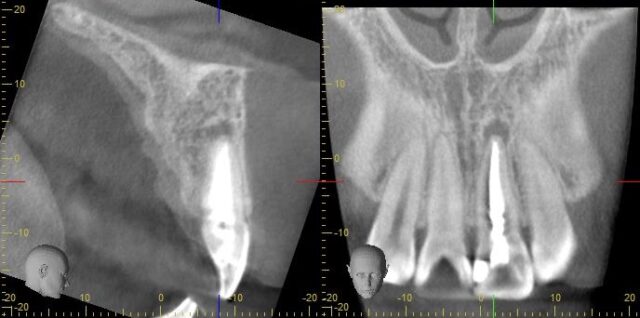

デンタル写真やCT写真でも見てみましょう

根っこの先に膿が溜まってしまっています。

現在症状などはないそうですが、根管治療のやり直しが必要となります。

また、解剖学的に表側、裏側共に丸みを帯びるように神経が通っているのですが、他院では歯の裏側に小さく穴を開けて治療が行われていたため、周りの神経が取り切れなかったと考えられます。

また、今回は根尖の先が破壊されてしまっていたので、MTAセメントを使って根管充填しました。